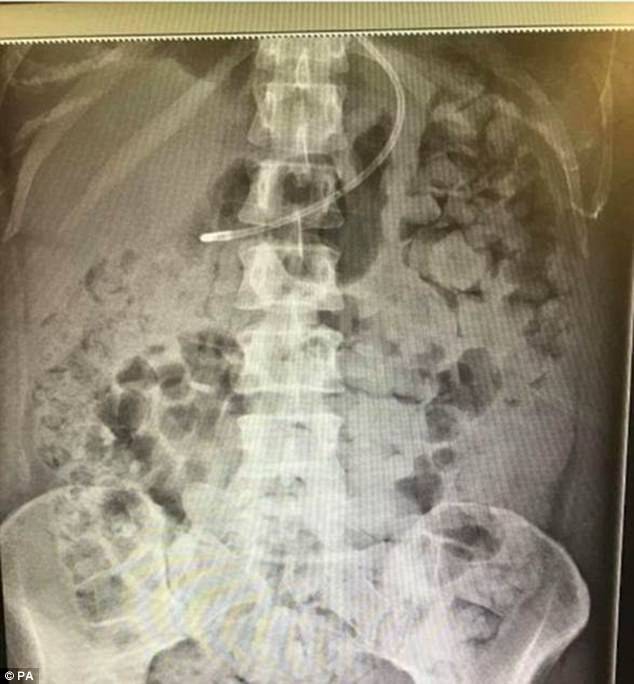

Doveva essere un piccolo intervento di routine, ma, complice un errore del chirurgo, è stato l’inizio di un vero e proprio incubo. Kelly Yeoman, 34enne di Bristol, in Inghilterra, e amazzone agonista, doveva rimuovere una cisti, e a tale scopo si è sottoposta a una piccola operazione all’ovaia. Purtroppo, qualcosa è andato storto durante l’intervento e la donna, ritrovatasi con l’intestino perforato, ha iniziato a vomitare le sue feci, come riportato da BBC News. Naturalmente il medico si è subito attivato per risolvere il problema, ma i suoi tentativi non hanno dato alcun esito. E così, ogni giorno la 34enne deve fare i conti con violenti attacchi di vomito, con tutto il disagio che è facile immaginare.

Nonostante siano trascorsi ormai diversi mesi dall’intervento, Yeoman si trova ancora in ospedale: il suo corpo si sta riempiendo di feci, la cui fuoriuscita è – a quanto pare – impossibile da arginare. Onde evitare l’insorgere di un’infezione, la donna viene sottoposta a trattamenti giornalieri per la rimozione delle feci, ma la sua famiglia teme ormai il peggio. E questo perché i medici sembrano non riuscire a trovare una soluzione a questo problema. Così, i parenti e amici della malcapitata hanno lanciato una campagna di raccolta fondi necessari per accedere a un centro specializzato di Londra: l’obiettivo da raggiungere è 10.000 sterline, pari a poco più di 11.000 euro. Con la speranza che ciò serva a restituirle una vita “normale”.